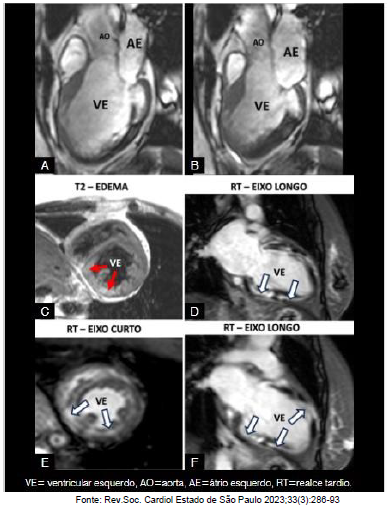

Paciente, 53 anos, sexo feminino, não hipertensa, não diabética, não tabagista, evoluindo com quadro de insuficiência cardíaca, do tipo restritiva de difícil controle, encaminhada para implante de marcapasso, devido a um Bloqueio atrioventricular (BAVT). Trouxe uma radiografia de tórax com micronódulos pulmonares difusos e um ecocardiograma feito no interior que mostrava uma miocardiopatia dilatada com FE=38%, com alterações segmentares de contratilidade. Cineangiocoronariografia normal. Foi solicitada a ressonância magnética cardíaca para esclarecimento diagnóstico, antes do implante do marcapasso e biópsia.

Enunciado 3842452-1

Após análise do caso clínico e da ressonância cardíaca realizada e apresentada acima, qual o diagnóstico mais provável?